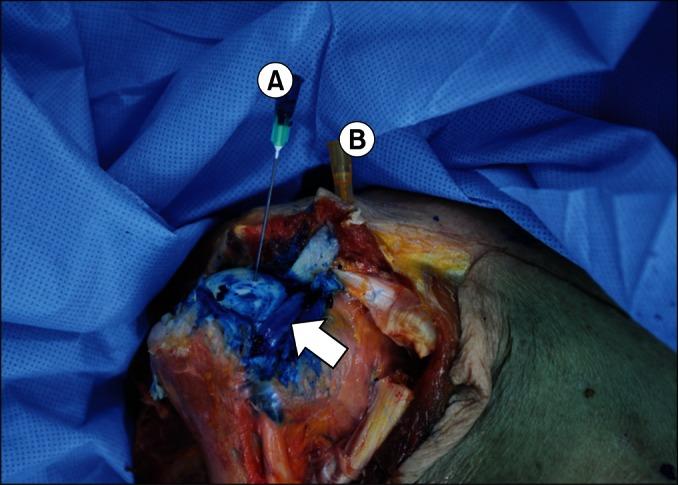

Twelve shoulders from 7 adult cadavers were anatomically dissected after a dye injection had been performed, while the cadavers were in the supine position. Before the injection, a clinician determined the injection point using the ultrasound and the more internal axial arm rotation was compared to how it was positioned in a previous study. Injection confidence scores and injection accuracy scores were rated.

The clinician's confidence score was high in 92% (11 of 12 shoulders) and the injection accuracy scores were 100% (12 of 12 shoulders). The long heads of the biceps tendons were not penetrated.

Indirect ultrasound guidance and positioning shoulder adducted at 10° and internally rotated at 60°-70° during the superior glenohumeral joint injection would be an effective method to avoid damage to the long head of biceps tendons and to produce a highly accurate injection.

对7具成年尸体的12个肩部进行解剖,尸体处于仰卧位,先进行染料注射。注射前,一名临床医生使用超声确定注射点,并将更多的内旋轴向手臂旋转与之前研究中的定位方式进行比较。对注射信心评分和注射准确性评分进行评定。

临床医生的信心评分在92%(12个肩部中的11个)较高,注射准确性评分达100%(12个肩部中的12个)。肱二头肌长头未被穿透。

在盂肱关节上方注射时,采用间接超声引导并将肩部内收10°、内旋60° - 70°定位,将是避免损伤肱二头肌长头并实现高度准确注射的有效方法。